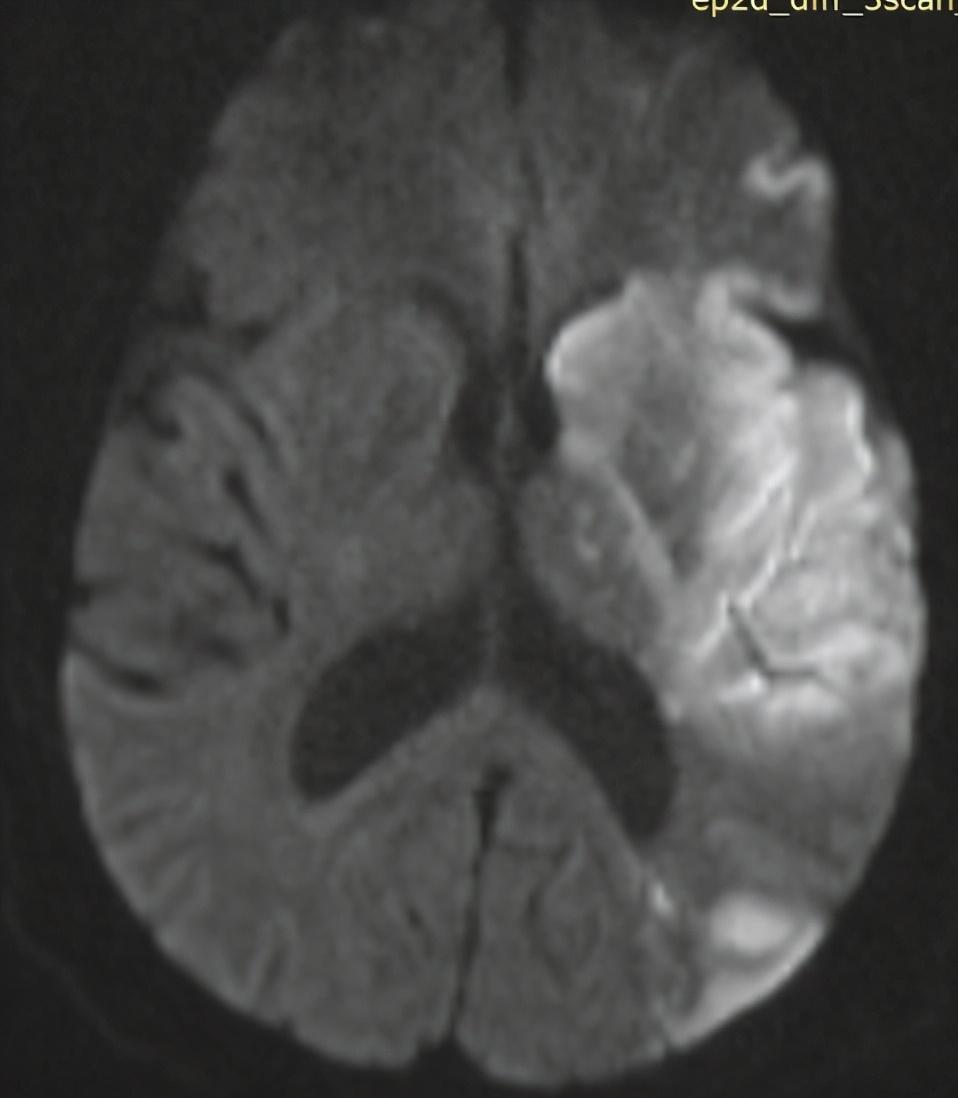

到了晚上凌晨上厕所时,老王突然“砰的一声”摔倒了,妻子闻声而至,发现人已经倒在地板上,呼喊没有反应,这时妻子慌了神,还好她记得马上拨打120急救电话,不然老王的命可能都没了。后来,老王被送到医院急诊,完善头颅CT检查提示左侧大脑大面积脑梗死,心电图提示心房颤动。

左侧大脑大面积脑梗死